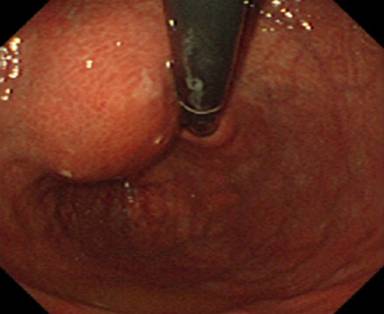

An endoscopy of the upper gastrointestinal tract showed a submucosal tumor, about 4 cm in diameter, located in the posterior wall of the gastric body (Figure 1). The results of the bioptic specimen could not be diagnosed pathologically. MRCP showed neither dilation nor irregularity of the main pancreatic duct (Figure 2). A CT scan demonstrated an ill-defined, irregular solid mass, 6x6x7 cm in size, situated between the retroperitoneum, the pancreas and the lesser curvature of the stomach (Figure 3). The tumor seemed to originate from the retroperitoneum with invasion of the stomach and pancreas. The left gastric artery and the splenic artery were compressed by the tumor which was located adjacent to the celiac axis. Celiac angiography indicated encasement of the splenic artery (Figure 4). Superior mesenteric artery angiography and portography were unremarkable. The tumor was essentially hypovascular. Although a definitive diagnosis was uncertain on the basis of the imaging findings described above, primary neoplasms including malignant mesenchymal tumors were taken into consideration preoperatively.

Figure 1. An endoscopic examination of the upper gastrointestinal tract showing a submucosal tumor, about 4 cm in diameter, located at the lesser curvature and the posterior wall of the upper gastric body. |